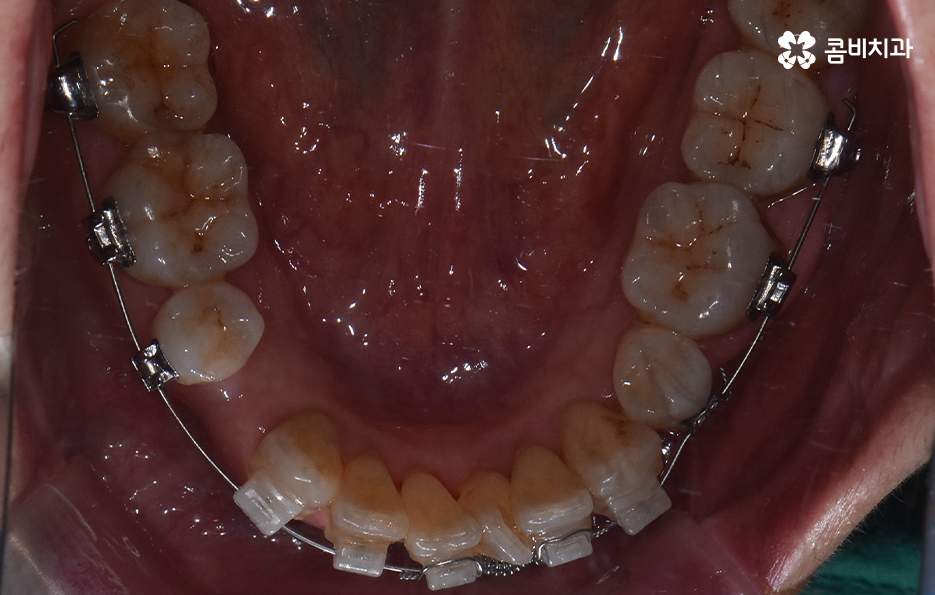

콤비교정은 윗니는 설측으로 진행하고 아랫니는 순측으로 교정기를 착용하기 때문에 웃을 때 주로 보이는 앞니는 교정기 착용이 티가 안난다는 점에서 크게 웃지 않는다면 교정기 착용이 거의 티가 안나는 수준으로 교정을 진행할 수 있어요

오늘 보시는 교정 사례의 경우를 보시면 아랫니의 틀어짐도 크지만 측면 사진으로 보시면 치열로 인해 돌출입에 영향을 준다는 사실도 알 수 있어요. 즉 치열과 함께 돌출입도 함께 고치고 싶어하기 때문에 치열도 재배열 하지만 치아 안쪽으로 넣어서 입술라인과 얼굴형으로 볼 때도 돌출입도 치료하는 치료 계획을 세웠기 때문에 작은 어금니 발치를 통한 치아의 이동 공간을 확보한 사례로 볼 수 있어요